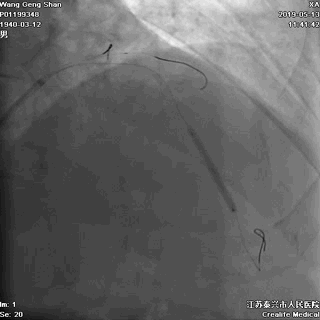

01 导丝进前三叉分支

对角支导丝到位

左冠共计5根导丝